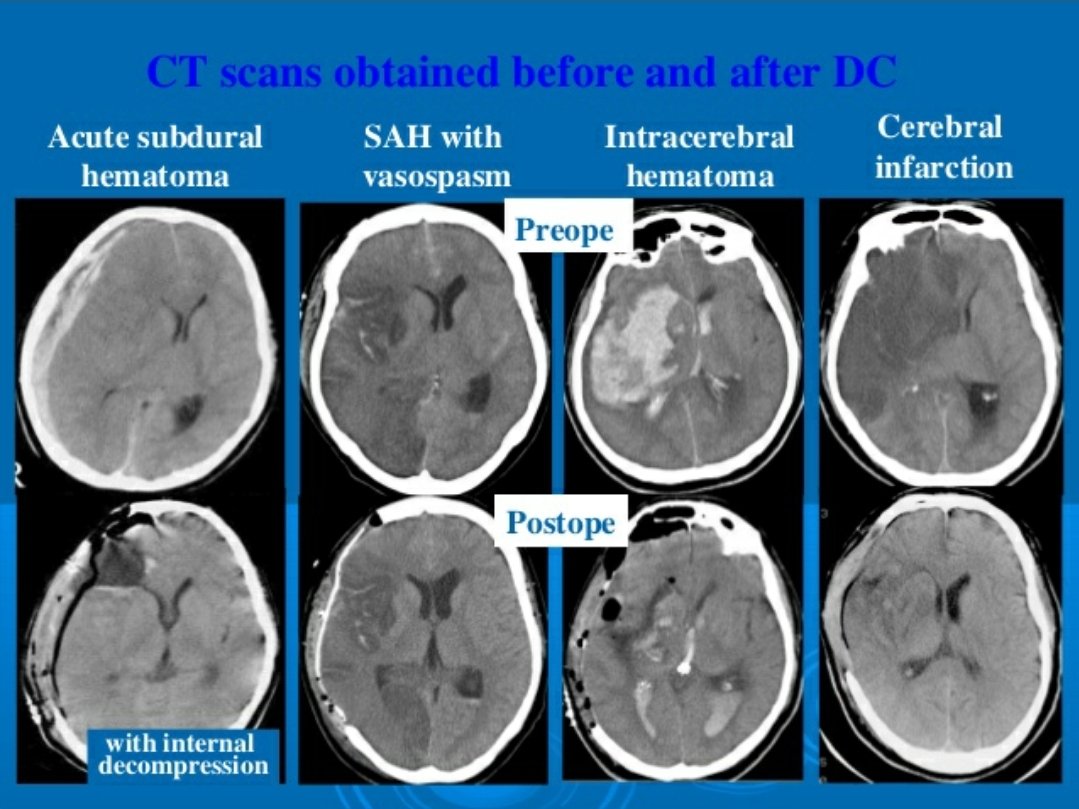

#السكته_الدماغيه_النزفيه

🧠علاجها

💥السيطرة ع #ضغط_الدم

💥السيطرة على سبب النزيف ومضاعفاته ( ان وجدت )

اما بالتدخل الجراحي او العلاجات الدوائيه او كلاهما

💥إيقاف علاجات السيوله ان وجدت

💥علاج المضاعفات ان وجدت ك #التشنجات او #الصداع او تضيق الشرايين العكسي

💥علاج السبب الاساسي

🧠علاجها

💥السيطرة ع #ضغط_الدم

💥السيطرة على سبب النزيف ومضاعفاته ( ان وجدت )

اما بالتدخل الجراحي او العلاجات الدوائيه او كلاهما

💥إيقاف علاجات السيوله ان وجدت

💥علاج المضاعفات ان وجدت ك #التشنجات او #الصداع او تضيق الشرايين العكسي

💥علاج السبب الاساسي